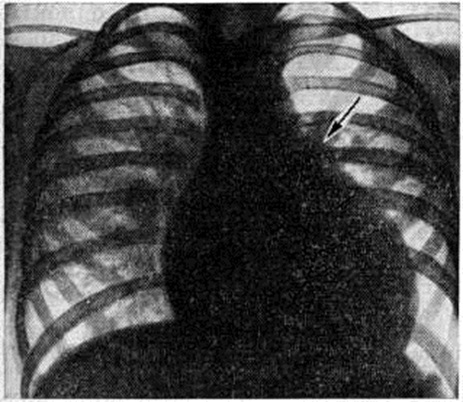

Диагноз. При аортальном стенозе данные векторкардиографии (смотри полный свод знаний) отражают подъём левожелудочкового давления лучше, чем ЭКГ. Только заметное повышение давления (градиент давления на уровне сужения более 60 миллиметров ртутного столба) приводит к появлению на ЭКГ признаков гипертрофии левого желудочка. У новорождённых на ЭКГ могут быть лишь признаки гипертрофии правого желудочка. Характерные клинические, симптомы в сочетании с признаками гипертрофии левого желудочка на ЭКГ указывают на выраженный аортальный стеноз (рисунок 3). При рентгенологическое исследовании у детей тень сердца нормальных размеров или с признаками гипертрофии левого желудочка. При высоком конечно-диастолическом давлении в левом желудочке и левом предсердии отмечаются застойные явления в прикорневых отделах лёгких. Может быть расширена восходящая часть аорты (постстенотическая дилатация). У детей с выраженным стенозом рентгенологически определяется аортальная конфигурация сердца (рисунок 4) и усиленный легочно-сосудистый рисунок. При ретроградной катетеризации сердца катетер проводят через место сужения в полость левого желудочка, измеряют градиент давления, выявляют место сужения и возможные сопутствующие пороки. У новорождённых и грудных детей катетеризация сердца может быть заменена эхокардиографическим исследованием (смотри полный свод знаний: Эхокардиография). У больных с асимметричной перегородочной гипертрофией во время систолы происходит смыкание передней створки левого предсердножелудочкового (митрального) клапана с гипертрофированным миокардом. Сужение может сопровождаться большим градиентом давления. При нагрузках, приёме сердечных гликозидов или инотропных средств и нитроглицерина градиент давления возрастает, но снижается при использовании р-адреноблокаторов (анаприлина, обзидана, индерала). Во время систолы, следующей после экстрасистолы, артериальное давление уменьшается, в то время как при других видах аортальногостеноза оно возрастает. При массивной мышечной гипертрофии возникает обструкция выходного отдела левого желудочка, нарушается функция митрального клапана. Признаки заболевания аналогичны таковым при других видах аортального стеноза, однако на ЭКГ всегда регистрируют выраженную гипертрофию левого желудочка, удлинение интервала Q — Г, изменения S — Г, зубцов Т и Q. Диагноз может быть установлен достаточно точно с помощью эхокардиографии. Во время катетеризации сердца на киноангиокардиограмме (смотри полный свод знаний: Ангиокардиография) в боковой проекции видно сужение полости левого желудочка в его выходной части. Детей с сердечной недостаточностью оперируют по жизненным показаниям. Так называемый плановые операции при аортальном стенозе выполняют, если в покое градиент давления на уровне сужения выше 60 миллиметров ртутного столба. Аортальную вальвулотомию производят либо по закрытой методике (через верхушку сердца в аорту последовательно проводят вальвулотом и дилататор), либо на «открытом» сердце в условиях умеренной гипотермии (общей или краниоцеребральной) при пережатых полых венах. Доступ — через стенку аорты. В течение 3—5 минут рассекают клапан по комиссурам. Безопаснее устранять порок в условиях искусственного кровообращения. Наибольшие трудности возникают при коррекции надклапанного сужения с гипоплазией аорты, что требует вшивания заплаты в стенку аорты, иногда с протезированием клапанов сердца (смотри полный свод знаний), и асимметричной гипертрофии миокарда. Иссечение мышечных масс может быть выполнено из аортального доступа, который иногда приходится дополнять рассечением стенки левого желудочка. Существуют методики, предусматривающие иссечение миокарда со стороны правого желудочка. К более радикальным операциям относится иссечение миокарда через левое предсердно-желудочковое отверстие с последующим протезированием митрального клапана. Ок. 10% неоперированных детей раннего возраста имеют явные признаки левожелудочковой недостаточности. В течение первого года жизни (особенно первого месяца) большая их часть погибает. У выживших со средней степенью сужения клинические, признаки Пороки сердца врождённые с возрастом нарастают. Страдающие тяжёлой формой стеноза в 1—7% случаев умирают внезапно. В 20% случаев при стенозе развивается регургитация. При асимметричной гипертрофии перегородки сердца продолжительность жизни ограничена 40—50 годами. Результаты оперативного лечения во многом определяются исходной степенью тяжести стеноза, его морфологией, состоянием миокарда левого желудочка, радикальностью оперативного вмешательства и отсутствием послеоперационной недостаточности клапана. Операционная летальность не превышает 10%. Через 10 лет около 25% оперированных нуждается в повторном вмешательстве для ликвидации рестеноза или регургитации. Во время повторных операций, как правило, производят протезирование клапана. У остальных отдалённые результаты хорошие и удовлетворительные: большая часть из них может считаться практически здоровыми. Аортолёгочный свищ — врождённое соустье между восходящей частью аорты и лёгочным стволом — относится к редким аномалиям (0,3% всех врождённых пороков «сердца.). На 8-й неделе у эмбриона формируется спиральная перегородка, которая при нормальном развитии делит общий артериальный ствол на два продольных канала (аорту и лёгочный ствол) и срастается в области их фиброзных колец с межжелудочковой перегородкой. Нарушения механизма образования перегородки приводят к появлению патологический отверстия между двумя магистральными сосудами. В большинстве случаев дефект располагается на 1—5 миллиметров выше фиброзного кольца устья аорты. Реже отверстие достигает клапанов аорты и лишь иногда располагается в дистальной х/3 восходящей части аорты. Размеры соустья варьируют широко — от 2 до 30 миллиметров. Отсутствие межсосудистой перегородки от клапанов аорты до дистального отдела восходящей части аорты может рассматриваться как общий артериальный ствол. Характер гемодинамических нарушений при аортолёгочном свище во многом сходен с расстройствами кровообращения при открытом артериальном протоке. Однако вследствие близости патологический отверстия к устью аорты (отверстие аорты) осложнения развиваются быстрее, в частности лёгочная гипертензия. Клиническая картина определяется размерами аортолёгочного свища и состоянием сосудов лёгких. При небольших размерах свища (менее 5 миллиметров) течение порока аналогично таковому при артериальном протоке. Однако эпицентр систолодиастолического шума при этом пороке располагается ближе к средней линии во втором межреберье у грудины. При средних размерах свища (6—10 миллиметров) клинические, проявления более тяжёлые, чем при артериальном протоке такого же диаметра. Отмечается бледность, ребёнок отстаёт в физическом развитии, у него легко возникает одышка, даже при небольших физических нагрузках; характерны слабость, повышенная утомляемость. Большой свищ (более 10 миллиметров) сопровождается высокой лёгочной гипертензией, поэтому возникновение цианоза, приступов одышки, нарушений ритма (вначале лишь при нагрузках) свидетельствует о выравнивании давления в аорте и лёгочном стволе и двустороннем шунтировании крови. В этот период может проявиться сердечная недостаточность. До развития лёгочной гипертензии (при малых и средних размерах свища) клинические, признаки порока во многом совпадают с проявлениями артериального протока (систолодиастолический шум, дрожание над сердцем и другие). При развитии лёгочной гипертензии вначале исчезает диастолический шум, а затем ослабевает и систолический. На ЭКГ в зависимости от степени нарушений гемодинамики определяются признаки перегрузки левого, обоих или преимущественно правого желудочка, нарушения сердечного ритма (пароксизмальная тахикардия, экстрасистолия). При рентгенологическое исследовании — изменения размеров сердца и сосудов лёгких взаимосвязаны с величиной и направлением сброса крови. При большом артериовенозном сбросе увеличены основание и левые отделы сердца, усилен лёгочный рисунок, выбухает дуга лёгочного ствола; при сбалансированном шунте наблюдается гипертрофия обоих желудочков, обеднение сосудистого рисунка по периферии лёгких. Катетеризация и контрастирование сердца являются основными методами распознавания порока и установления степени нарушений гемодинамики. Катетер, проведённый из правого желудочка в лёгочный ствол, может попасть через свищ в аорту. В зависимости от величины давления в аорте и лёгочном стволе контрастирование одной из них может дать полное представление о локализации, размерах, направлении и объёме шунта. Для этой цели производят аортографию (смотри полный свод знаний) в прямой и правой косой позиции (с помощью катетера, проведённого ретроградно до клапана аорты). Величина сброса крови может быть установлена также исследованием её на насыщение кислородом в различных участках правых отделов сердца и лёгочном стволе красочными, платиноводородными и термодилюционными пробами. Порок следует дифференцировать с открытым артериальным протоком (смотри полный свод знаний), дефектом межжелудочковой перегородки, стенозом лёгочной артерии, стенозом устья аорты, недостаточностью митрального клапана, разрывом аневризмы синуса Вальсальвы, аневризмами коронарных сосудов, артериовенозными аневризмам левой внутригрудной, межрёберных артерий или перикардиальных сосудов. Лечение оперативное, за исключением больных с выраженной лёгочной гипертензией и преобладающим венозно-артериальным сбросом крови (им показано ограничение в физических нагрузках и терапия сердечной недостаточности). Для закрытия свища существует несколько способов. Свищ, расположенный выше аорты и клапанов лёгочного ствола, перевязывают несколькими лигатурами. Если свищ прилегает к клапану аорты, то его можно ушить со стороны лёгочного ствола (рисунок 5) в условиях умеренной гипотермии с выключением сердца из кровообращения. В большинстве же случаев операция при аортолёгочном свище проводится в условиях искусственного кровообращения. В зависимости от размеров отверстия и продолжительности операции применяется один из видов защиты миокарда (холодовая или медикаментозная кардиоплегия, коронарная перфузия и тому подобное). При дистально пережатых сосудах производят либо ушивание свища, либо вшивание заплаты (что предпочтительно) со стороны аорты или лёгочного ствола. Неоперированные больные с лёгочной гипертензией обычно погибают в детском возрасте. Летальность после операций у больных без выраженной лёгочной гипертензии не превышает 5%, у больных с лёгочной гипертензией более 50%. Результаты в отдалённые сроки после операции в подавляющем большинстве случаев благоприятные. Артериальный проток соединяет аорту с лёгочным стволом. Необходимый в период эмбрионального развития для нормального кровообращения, после рождения ребёнка он облитерируется. Если облитерация не наступает, развиваются нарушения гемодинамики, сброс крови из аорты в лёгочный ствол. Лечение оперативное (смотри полный свод знаний: Артериальный проток). Атрезия лёгочного ствола в сочетании с дефектом межжелудочковой перегородки представляет собой одну из форм тетрады Фалло. Обычно наблюдается гипоплазия правого желудочка (I тип); возможно сочетание нормального или даже расширенного правого желудочка с несостоятельностью трёхстворчатого клапана (II тип). Клапан лёгочного ствола маленький, заращён. Дистальнее его ствол сосуда сохранен. Центральный кровоток осуществляется через дефект перегородки в левые отделы сердца и аорту, далее через артериальный проток в сосуды лёгких. Артериальный проток обычно узкий. Степень цианоза зависит от величины сброса крови через артериальный проток. Цианоз заметен с момента рождения, усиливается с развитием сердечной недостаточности; наблюдаются приступы гипоксии, ацидоз. На ЭКГ отмечаются признаки преобладания левого желудочка, особенно при I типе порока. Рентгенологические исследование выявляет увеличение размеров сердца, лёгочно-сосудистый рисунок ослаблен. При контрастировании сердца виден правый желудочек с выходным отделом в виде слепого мешка и регургитацией в предсердие. Этот порок нужно дифференцировать с трикуспидальной атрезией, тетрадой Фалло, стенозом лёгочного ствола, транспозицией крупных сосудов со стенозом лёгочного ствола. Лечение оперативное. Если правый желудочек недоразвит, то целесообразно наложить межсосудистый анастомоз; если он развит нормально, то производят лёгочную вальвулотомию. В некоторых случаях между правым желудочком и лёгочным стволом вшивают кондуит (консервированный в глутаровом альдегиде биологический трансплантат клапана сердца, вшитый в сосудистый протез). Послеоперационная летальность у новорождённых с гипоплазированным правым желудочком высокая (до 80%). Без операции практически все дети погибают в течение первого года жизни. Атрезия устья аорты сочетается с гипоплазией восходящей части аорты, гипоплазией или атрезией левого желудочка и атрезией или выраженным стенозом митрального клапана. Устья коронарных артерий, как правило, располагаются в луковице аорты. Для поддержания жизни необходимы артериальный проток и дефект межпредсердной перегородки (открытое овальное окно). Кровообращение при этом происходит следующим образом: венозная кровь большого и малого круга кровообращения смешивается в предсердии, поступает в правый желудочек, лёгочный ствол и через артериальный проток в аорту. Аортальная атрезия и другие варианты гипоплазии левых отделов сердца являются самой частой причиной смерти новорождённых с Пороки сердца врождённые Хотя при рождении ребёнок может выглядеть нормально, вскоре выявляется сердечная недостаточность с дилатацией правого желудочка, падением АД и цианозом. Данные физикального, электрокардиографического и рентгенологическое исследований далеко не всегда позволяют правильно распознать порок. Только эхокардиография, катетеризация сердца и киноангиокардиография дают возможность поставить окончательный диагноз и оценить гемодинамические нарушения. Порок считается неизлечимым, оперативное вмешательство не проводится. Большая часть новорождённых с этой патологией погибает в течение нескольких дней после рождения. Атриовентрикулярный канал (неполная форма) представляет собой сочетание первичного дефекта межпредсердной перегородки с расщеплением створки митрального или трёхстворчатого клапана или створок обоих клапанов. Первичный дефект межпредсердной перегородки всегда большой, имеет полулунную форму, сверху отграничен межпредсердной перегородкой, снизу фиброзным кольцом клапанов. Передняя створка митрального клапана расщеплена обычно в середине общей части фиброзного кольца клапана. Аналогично может быть изменена и перегородочная створка трёхстворчатого клапана.. Нарушения гемодинамики аналогичны таковым при первичном дефекте межпредсердной перегородки. Расщепление створки клапана приводит к регургитации крови из желудочка (или обоих желудочков) в оба предсердия; степень регургитации может быть различной. Для детей в возрасте до 3 лет при этом пороке характерна сердечная недостаточность, которая сопровождается одышкой, низкой толерантностью к физическим нагрузкам, резким отставанием в развитии ребёнка. У взрослых, как правило, наблюдаются хронический недостаточность кровообращения, приступы пароксизмальной тахикардии, присоединяется инфекционные эндокардит. Основные физикальные признаки порока: бледность кожи, «сердечный горб», интенсивный систолический шум над верхушкой сердца, расщепленный 11 тон над лёгочным стволом. На ЭКГ выявляются неполная блокада правой ножки пучка Гиса, отклонение электрической оси влево при наличии диастолической перегрузки правого желудочка; на ФКГ — интенсивный систолический шум над верхушкой сердца, расщепление II тона с усилением лёгочного компонента. Рентгенологически отмечается увеличение обоих желудочков, нередко кардиомегалия. При катетеризации сердца обнаруживают низкий дефект межпредсердной перегородки и регургитацию из желудочка при заполнении его контрастным веществом. Лечение — оперативное: из правосторонней торакотомии (смотри полный свод знаний) или срединной стернотомии (смотри полный свод знаний: Медиастинотомия) в условиях искусственного кровообращения расщепленную створку клапана соединяют отдельными П-образными швами, стремясь не сузить клапан. Дефект межпредсердной перегородки закрывают заплатой.